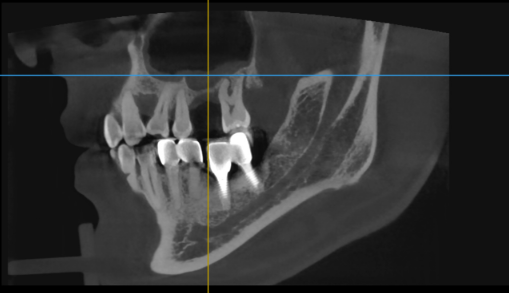

왼쪽 어금니 임플란트가 빠진 지 오래되어 김포 서울케이치과에 내원하신 40대 남성분의 상악동 골이식 사례를 소개해 드리겠습니다.

<치료 전>

왼쪽 어금니 부위(사진상 오른 쪽)의 파노라마 엑스레이를 보면 상악동 때문에 잇몸뼈가 거의 없습니다.

임플란트를 심기위해서는 상악동 골이식이 필요합니다.